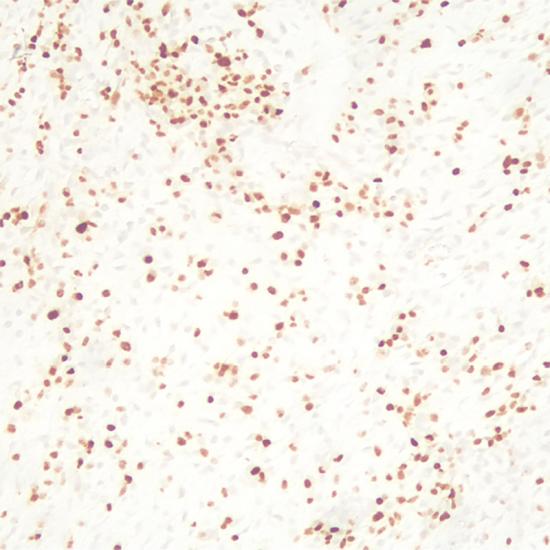

NKX2.2

NKX2.2抗體試劑(免疫組織化學(xué)法) 閩廈械備20190289號

• 陽性部位:

細(xì)胞核

• 陽性對照:

胰腺組織

NKX2.2是轉(zhuǎn)錄因子NKX家族中的一員,對中樞神經(jīng)系統(tǒng)和胰腺神經(jīng)內(nèi)分泌分化非常重要,表達(dá)于人的腦、胰腺、垂體和胃腸道等正常組織。NKX2.2對尤文氏肉瘤具有高敏感性和特異性,有助于尤文氏肉瘤的診斷和鑒別診斷。